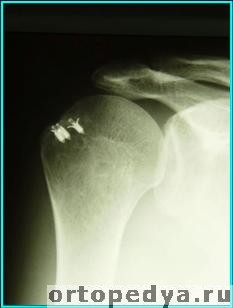

На послеоперационной рентгенограмме с титанами фиксаторами:

При использовании рассасывающихся якорей на снимке они не видны.